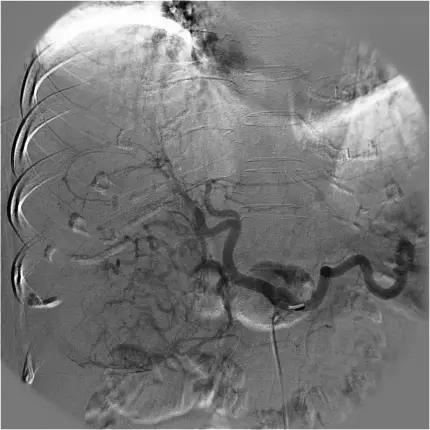

64歲女性,因急性右上腹部劇痛,掛急診求醫,腹部 CT 和血管攝影影像如附圖,則最可能的診斷為下列何者?

自發性肝腫瘤破裂導致急性腹痛與血性腹水的影像診斷

以動態對比增強CT與血管攝影判讀肝內高血管性病灶的特徵,區分肝細胞癌、肝內血管瘤、肝膿瘍或脂肪分布異常。

影像分析:

- 肝動脈攝影:右肝動脈分支顯示明顯腫瘤染色(tumor blush)以及不規則新生血管叢,伴隨可疑的對比劑外滲,提示活動性出血來源於高血管性病灶(ajronline.org)。